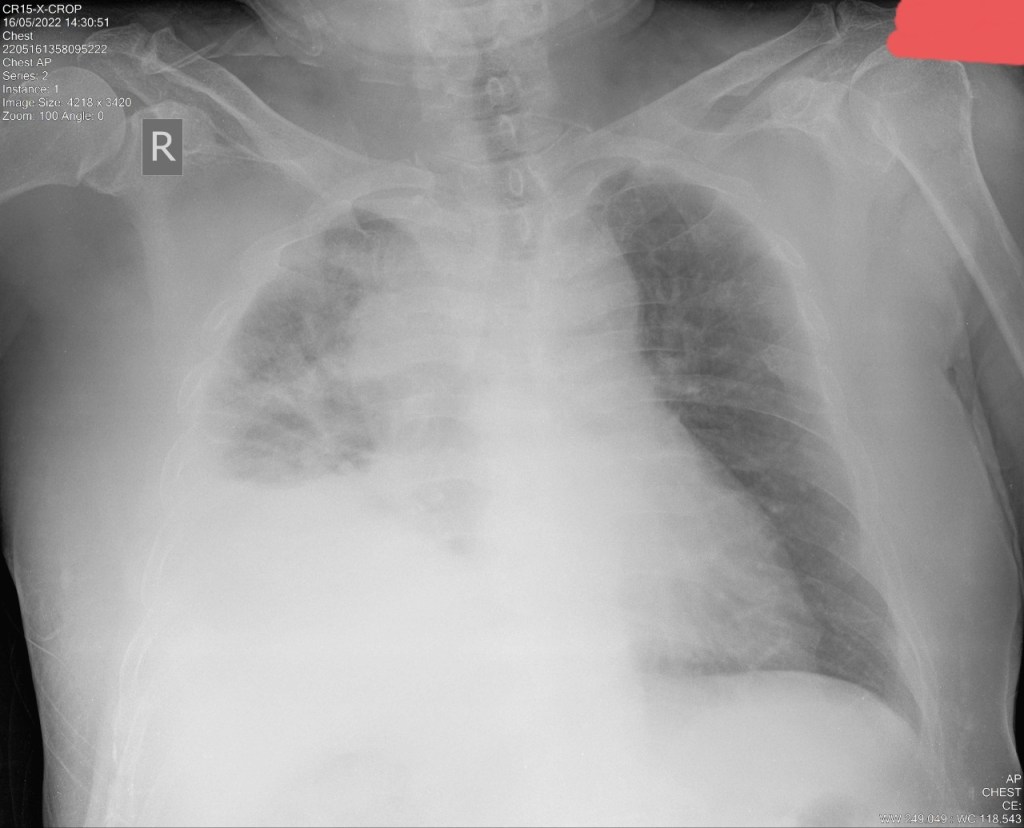

a. Konsolidasi

– Akut : pneumonia, aspirasi, infark, edem

-Kronik: limfoma, pneumonia, sarkoidosis

-Batwing: edema, pneumonia bakterialis, PCP (Pneumonia Pneumocystis), pneumonia viral